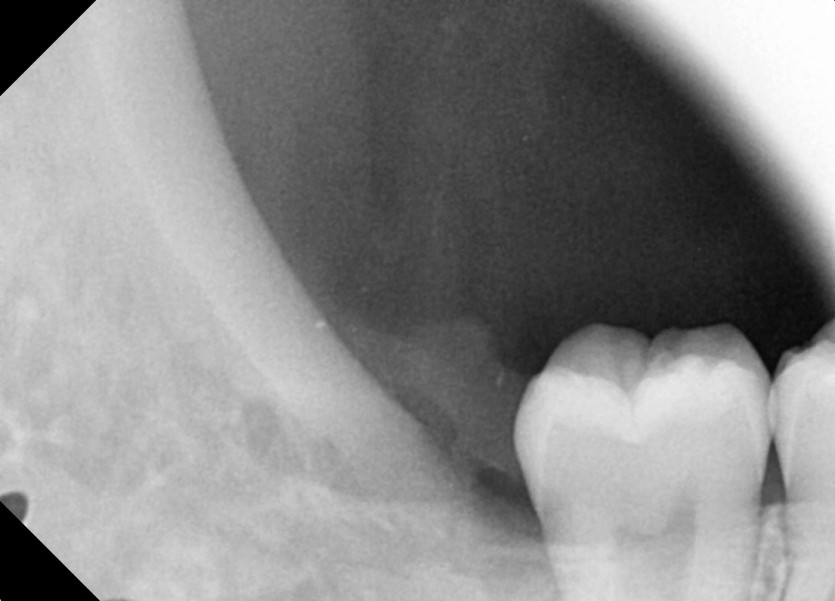

#18,48 사랑니 발치

구강 외과 전문의가 당일 발치했습니다.